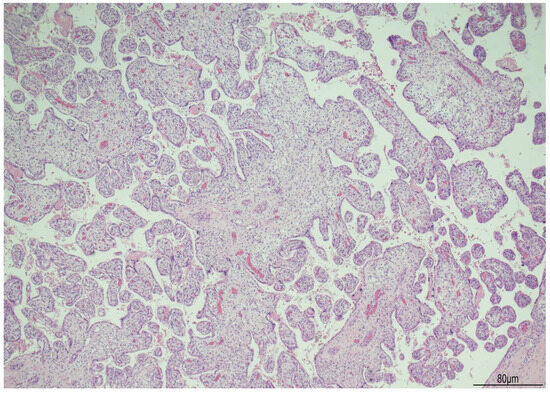

Background: The purpose of this study was to examine the relationship between qualitative characteristics and quantitative parameters from contrast-enhanced ultrasound (CEUS) and microvessel density (MVD) in hepatoblastoma (HB), as well as to investi...